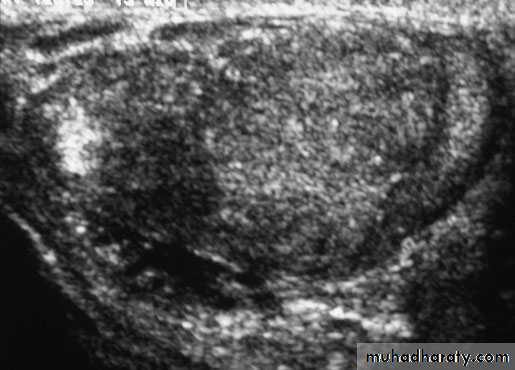

TUMOURS OF THE TESTES

Most testicular neoplasms are malignant

It is one of the most common forms of cancer in young men.Maldescent predisposes to malignancy

Clinical features

testicular lump which is usually painlesssensation of heaviness occurs when the testis is two or three times its normal size

The testis is enlarged, smooth, firm and heavy

Secondary hydrocele

Investigations

U/S scanning of the testis